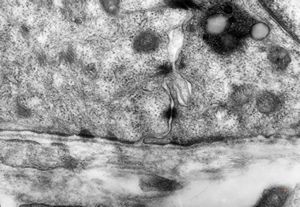

F, 48y. | lupus erythematodes … multiplicated vascular basement membrane

F, 48y. | lupus erythematodes … multiplicated vascular basement membrane

F, 48y. | lupus erythematodes … multiplicated vascular basement membrane